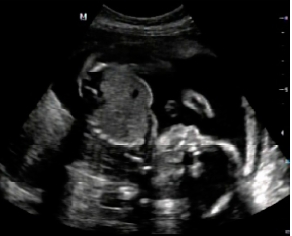

ahoj holky, tak mám za sebou další úspěšnou kontrolu u pana doktora, miminko roste jako z vody, už má prý skoro 0,5kg.

na utz bylo vše krásně vidět, detail chodila a dokonce si ten náš prcek cucal palec na ruce, a pak na mě máva, jako by to škvrně tušilo, že se na něj díváme a bude se fotit.

týden již cím pohyby hlavně na pravé straně břicha - pan doktor potvrdil, že tam má nožičky a hlavičku ne mém levém boku břichu.

bylo to nádherné, má se čile k světu, je to náš poklad.

pan doktor mi chěl říci pohlaví, ale já ho vědět a ani manžel nechceme, tak si to nechal pro sebe.

také mi dělal 3d utz, ale tam jsem toho moc neviděla. ten 2d mi přijde mnohem přehlednější.

mějte se krásně přikládám fotku -